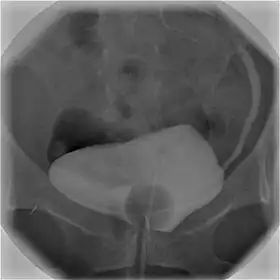

![]() Cystography image showing contrast in the urinary bladder and left ureter (right side of image). | |

Cystourethrography is a radiographic, fluoroscopic medical procedure that is used to visualize and evaluate the bladder and the urethra.[1] Voiding and positive pressure cystourethrograms help to assess lower urinary tract trauma, reflux, suspected fistulas, and to diagnose urinary retention. Magnetic imaging (MRI) has been replacing this diagnostic tool due to its increased sensitivity.[2] This imaging technique is used to diagnose hydronephrosis, voiding anomalies, and urinary tract infections in children. abnormalities.[3]